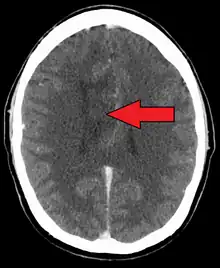

| A oligoastrocytoma on CT | |

An X-ray computed tomography (CT) or magnetic resonance imaging (MRI) scan is necessary to characterize the anatomy of this tumor as to size, location, and its heter/homogeneity. However, final diagnosis of this tumor, like most tumors, relies on histopathologic examination (biopsy examination).[3]